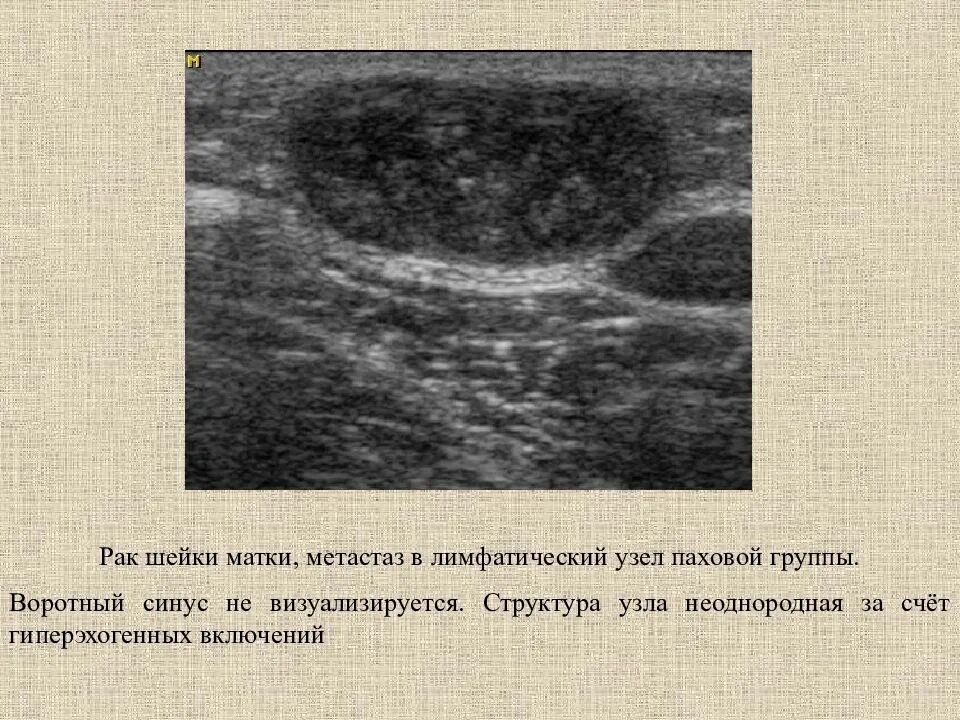

Метастазы в матке